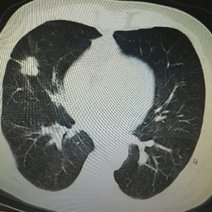

胸片怎么看

学会看胸片是临床医生必备的技能之一,首先,看胸壁的X线表现,观察胸壁软组织有大的肿块,有皮下积液、积气,同时观察肋骨的连续性是否有中断,这是肋骨骨折的X线征象...73227人收听

在临床上胸部X光片检查是常用的一种检查方法,它是利用X线产生图像,从而观察胸部的病变。胸片的观察需要按一定的顺序,一般可以按照从上往下的顺序,观察双肺上叶...1人收听